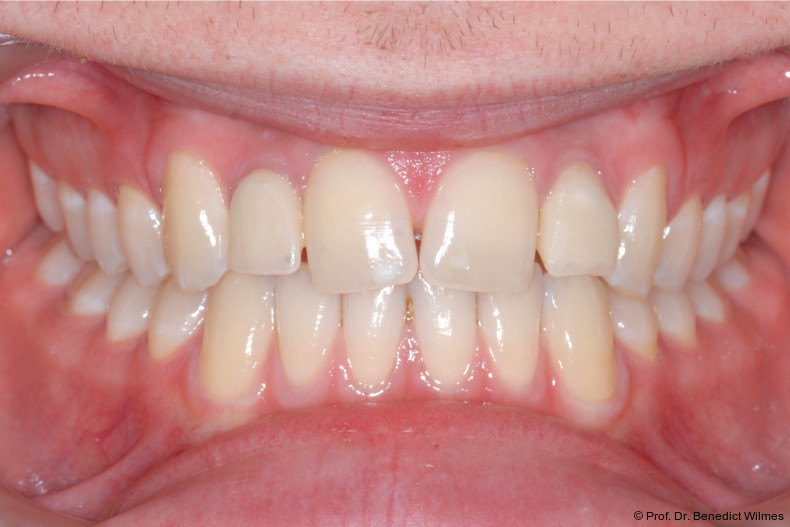

Ein 14-jähriger Patient wurde bei Aplasie der beiden oberen seitlichen Schneidezähne mit dem Ziel der beidseitigen Lückenöffnung kieferorthopädisch therapiert (Abb. 1a+b). Zum Ende der kieferorthopädischen Behandlung wurden zwei Miniimplantate in Regio 2er als temporärer Zahnersatz inseriert (Benefit System, PSM, 2 x 13 mm, Abb. 2a+b). Nach Abdrucknahme wurden Kronen auf den Peek-Abutments modelliert und diese mit Kunststoff auf die Abutments geklebt (Abb. 3a–d). In den Abbildungen 3 und 4 sind die klinischen und röntgenologischen Nachkontrollen innerhalb der nächsten achteinhalb Jahre dokumentiert. Man erkennt einen sowohl in der Höhe als auch in bukkopalatinalen Breite verbleibenden gesunden Knochen ohne Anzeichen einer Atrophie. Im Alter von 23 Jahren wurden die definitiven Implantate ohne die Notwendigkeit einer Augmentation eingesetzt (Abb. 5) und nach Einheilung prothetisch versorgt (Abb. 6a–e und Abb. 7a–c).